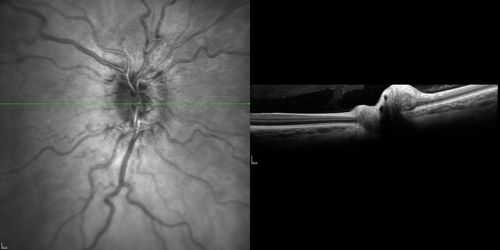

Optic Nerve (Disc) Drusen - Spectral Domain Optical Coherence Tomography Line Scan

34 Year Old woman no headaches normal vision

Optic Nerve Drusen - Buried and Not Calcified - Optical Coherence Tomography